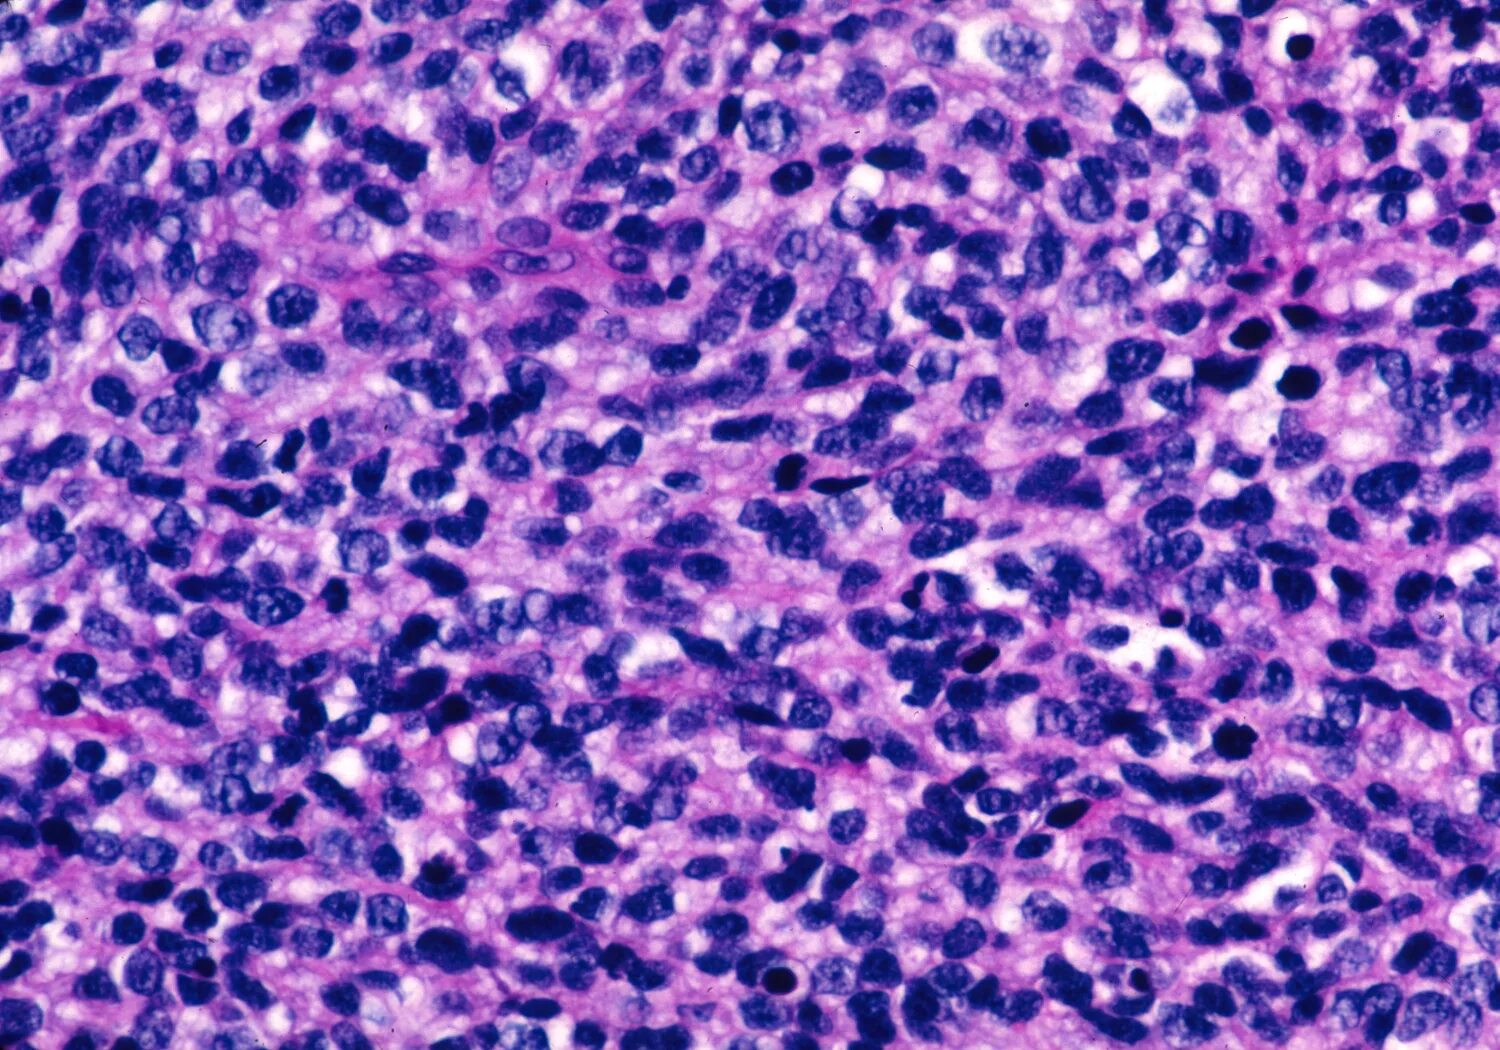

Синовиомы